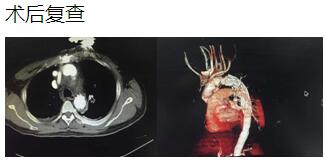

患者是一位48岁中年男性,因胸痛1小时入院,我院CT提示主动脉夹层累及胸、腹主动脉全层,诊断为主动脉夹层(D ebaKey I型)。患者病情危重,手术治疗是挽救其生命的唯一希望。为了挽救病人生命,经过麻醉科、手术室、体外循环组的术前充分讨论,心胸外科廖金文主任、廖承辉副主任带领团队决定为其施行复杂而高难度的浅低温停循环下“孙氏手术”。术中见主动脉全程及三分支受累,右冠受累,冠脉开口受压狭窄,予以行“升主动脉 主动脉弓置换 降主动脉术中支架置入术”,团队成员历经约10个小时的奋战,手术顺利完成。术后六小时患者意识完全清醒,现在已完全康复。